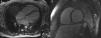

Cardiac magnetic resonance imaging (MRI) showed a slightly dilated LV with severe LV systolic dysfunction (LV ejection fraction 21%), together with anterolateral subendocardial delayed enhancement, possibly due to fibrosis, and slight RV dilatation (EDD 50mm) with severe systolic dysfunction (Figure 3).